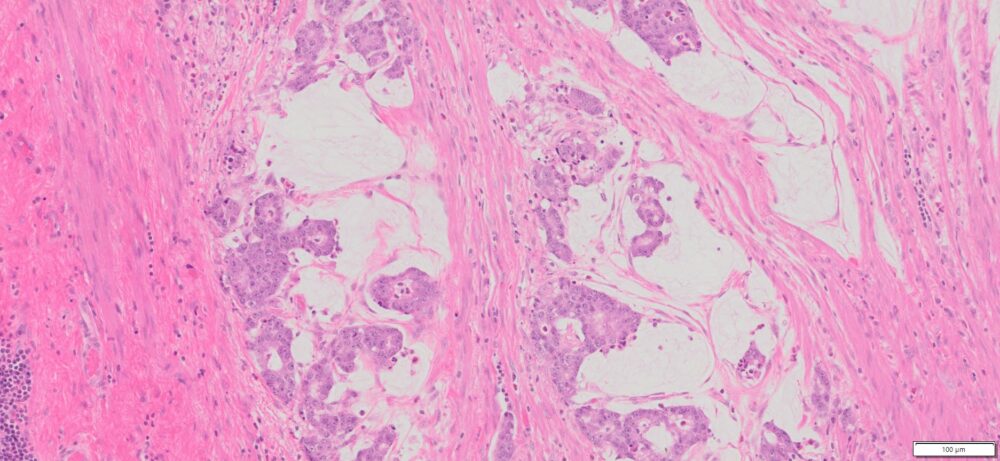

| Tissue | Pathology Diagnosis | Gender/ Age (year) | %Tumor Area | Tumor Grade | TMN/Stage | IHC data | |

| Appendix | Human Appendix Mucinous Adenocarcinoma | Male/68 | 10% | II |

|

MLH1,2,and 6, PMS2 show intact nuclear expression |